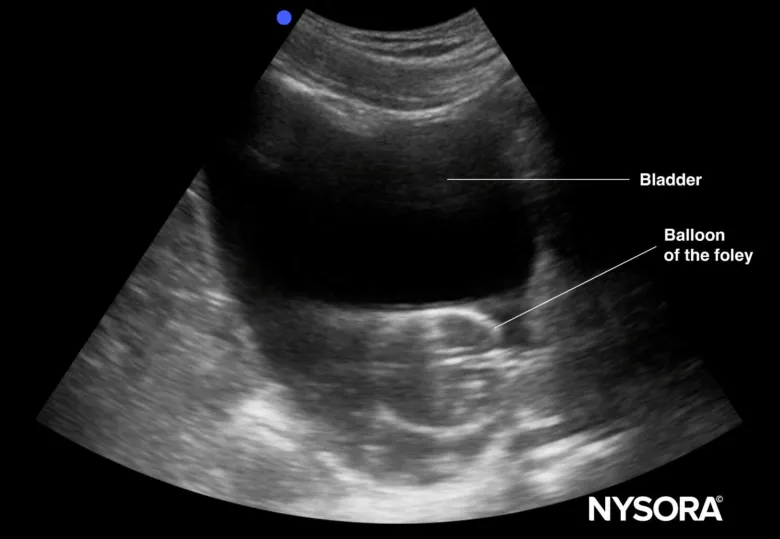

I cateteri di Foley sono un dispositivo medico comune ma spesso frainteso. Se siete mai stati in una situazione in cui tu o una persona cara avete bisogno, potresti aver sentito un mix di confusione e preoccupazione. Abbassiamo quali sono i cateteri Foley, perché sono usati e cosa dovresti sapere se ti trovi in questa situazione. Innanzitutto, ci rivolgiamo all'elefante nella stanza: la necessità di un catetere Foley spesso deriva da condizioni mediche che richiedono l'urina di drenaggio. Ciò potrebbe essere dovuto a un intervento chirurgico, alla ritenzione urinaria o persino a alcune condizioni neurologiche. Il pensiero di avere un catetere può essere scoraggiante, ma capire il suo scopo può alleviare un po 'di ansia. Ora, tuffiamoci nella funzionalità di un catetere Foley. Al centro, è un tubo flessibile che viene inserito nella vescica attraverso l'uretra. Questo tubo ha un piccolo pallone alla fine che lo mantiene in posizione. Una volta che è dentro, l'urina può drenare in una borsa da raccolta, consentendo comfort e igiene durante il recupero o il trattamento. Ecco una rapida panoramica del processo: 1. ** Inserimento **: un professionista sanitario pulirà l'area e inserirà delicatamente il catetere. Questo passaggio è cruciale per prevenire le infezioni. 2. ** Inflazione **: una volta che il catetere è nella vescica, il palloncino è gonfiato. Questo lo fissa in atto, garantendo che non scivolerà fuori. 3. ** Monitoraggio **: dopo l'inserimento, è essenziale monitorare l'output. Ciò può fornire preziose informazioni sull'idratazione del paziente e sulla funzione renale. 4. ** Rimozione **: quando non è più necessario, il palloncino viene sgonfiato e il catetere viene rimosso delicatamente. Questo di solito è un processo rapido e può essere fatto senza molto disagio. È importante ricordare che mentre i cateteri di Foley sono generalmente sicuri, si presentano alcuni rischi, come le infezioni del tratto urinario o il disagio. Comunicare con il proprio operatore sanitario su eventuali preoccupazioni può aiutare a gestire questi rischi in modo efficace. In sintesi, i cateteri Foley svolgono un ruolo vitale nelle cure mediche, specialmente quando si tratta di gestire le esigenze urinarie. Comprendere la loro funzionalità può trasformare una situazione stressante in una più gestibile. Se mai ti trovi a bisogno, ricorda che non sei solo, e c'è un intero squadra pronto a supportarti attraverso il processo.

I cateteri di Foley sono spesso trascurati, ma svolgono un ruolo cruciale nelle cure mediche. Ricordo la prima volta che ne ho incontrato uno durante il mio allenamento. È stato un po 'scoraggiante, ma capire il suo scopo e il suo design hanno fatto la differenza. Molte persone potrebbero non rendersi conto che i cateteri di Foley sono essenziali per i pazienti che hanno bisogno di assistenza per la minzione, in particolare per quelli che si stanno riprendendo da un intervento chirurgico o che si occupano di determinate condizioni mediche. Il disagio e le complicanze che possono derivare dalla ritenzione urinaria sono veri punti deboli per i pazienti. È qui che entrano in gioco il design e la funzionalità dei cateteri Foley. Innanzitutto, parliamo del design. Un catetere Foley è in genere realizzato con materiali flessibili e ha un palloncino sulla punta che lo mantiene saldamente in posizione. Questo design aiuta a prevenire le perdite e garantisce che il catetere rimanga dove deve essere. Sapere questo può alleviare le menti di pazienti e caregiver, poiché riduce la paura di potenziali incidenti. Successivamente, il processo di inserimento è cruciale. Molti pazienti si preoccupano del disagio associato al cateterismo. Tuttavia, l'uso di una tecnica sterile e l'applicazione di un lubrificante può minimizzare significativamente il disagio. È importante per i caregiver comunicare con i pazienti durante il processo, spiegando ogni passaggio per alleviare l'ansia. Dopo l'inserimento, il monitoraggio è la chiave. Ho visto in prima persona quanto sia fondamentale tenere d'occhio la produzione di urina e qualsiasi segni di infezione. Controlli regolari possono aiutare a identificare i problemi in anticipo, garantendo che i pazienti rimangano comodi e sicuri. Infine, quando è il momento di rimuovere il catetere, farlo delicatamente e seguire protocolli adeguati è essenziale. Ciò può impedire qualsiasi disagio e complicazioni inutili. In sintesi, i cateteri di Foley sono più che semplici dispositivi medici; Sono vita per molti pazienti. Comprendere il loro design e un uso corretto può trasformare un'esperienza scoraggiante in una gestibile. Affrontando le preoccupazioni comuni e fornendo una comunicazione chiara, possiamo aiutare i pazienti a navigare con fiducia nel loro recupero. Abbiamo una vasta esperienza nel settore del settore. Contattaci per consulenza professionale: Dylan Wang: sales@raycare-med.com/whatsapp +8615867465464.